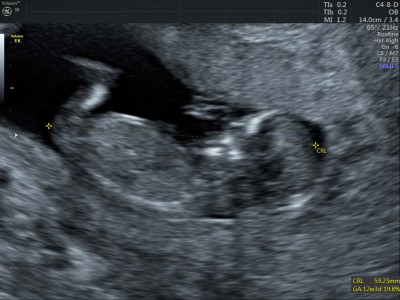

Bebeğim burda 12, haftalık cinsiyet tahmini yapmayı sevenler yorum yapabilir mi:)

bu bebis kiz

Tahmininiz doğru çıktı kızımız oluyor:)